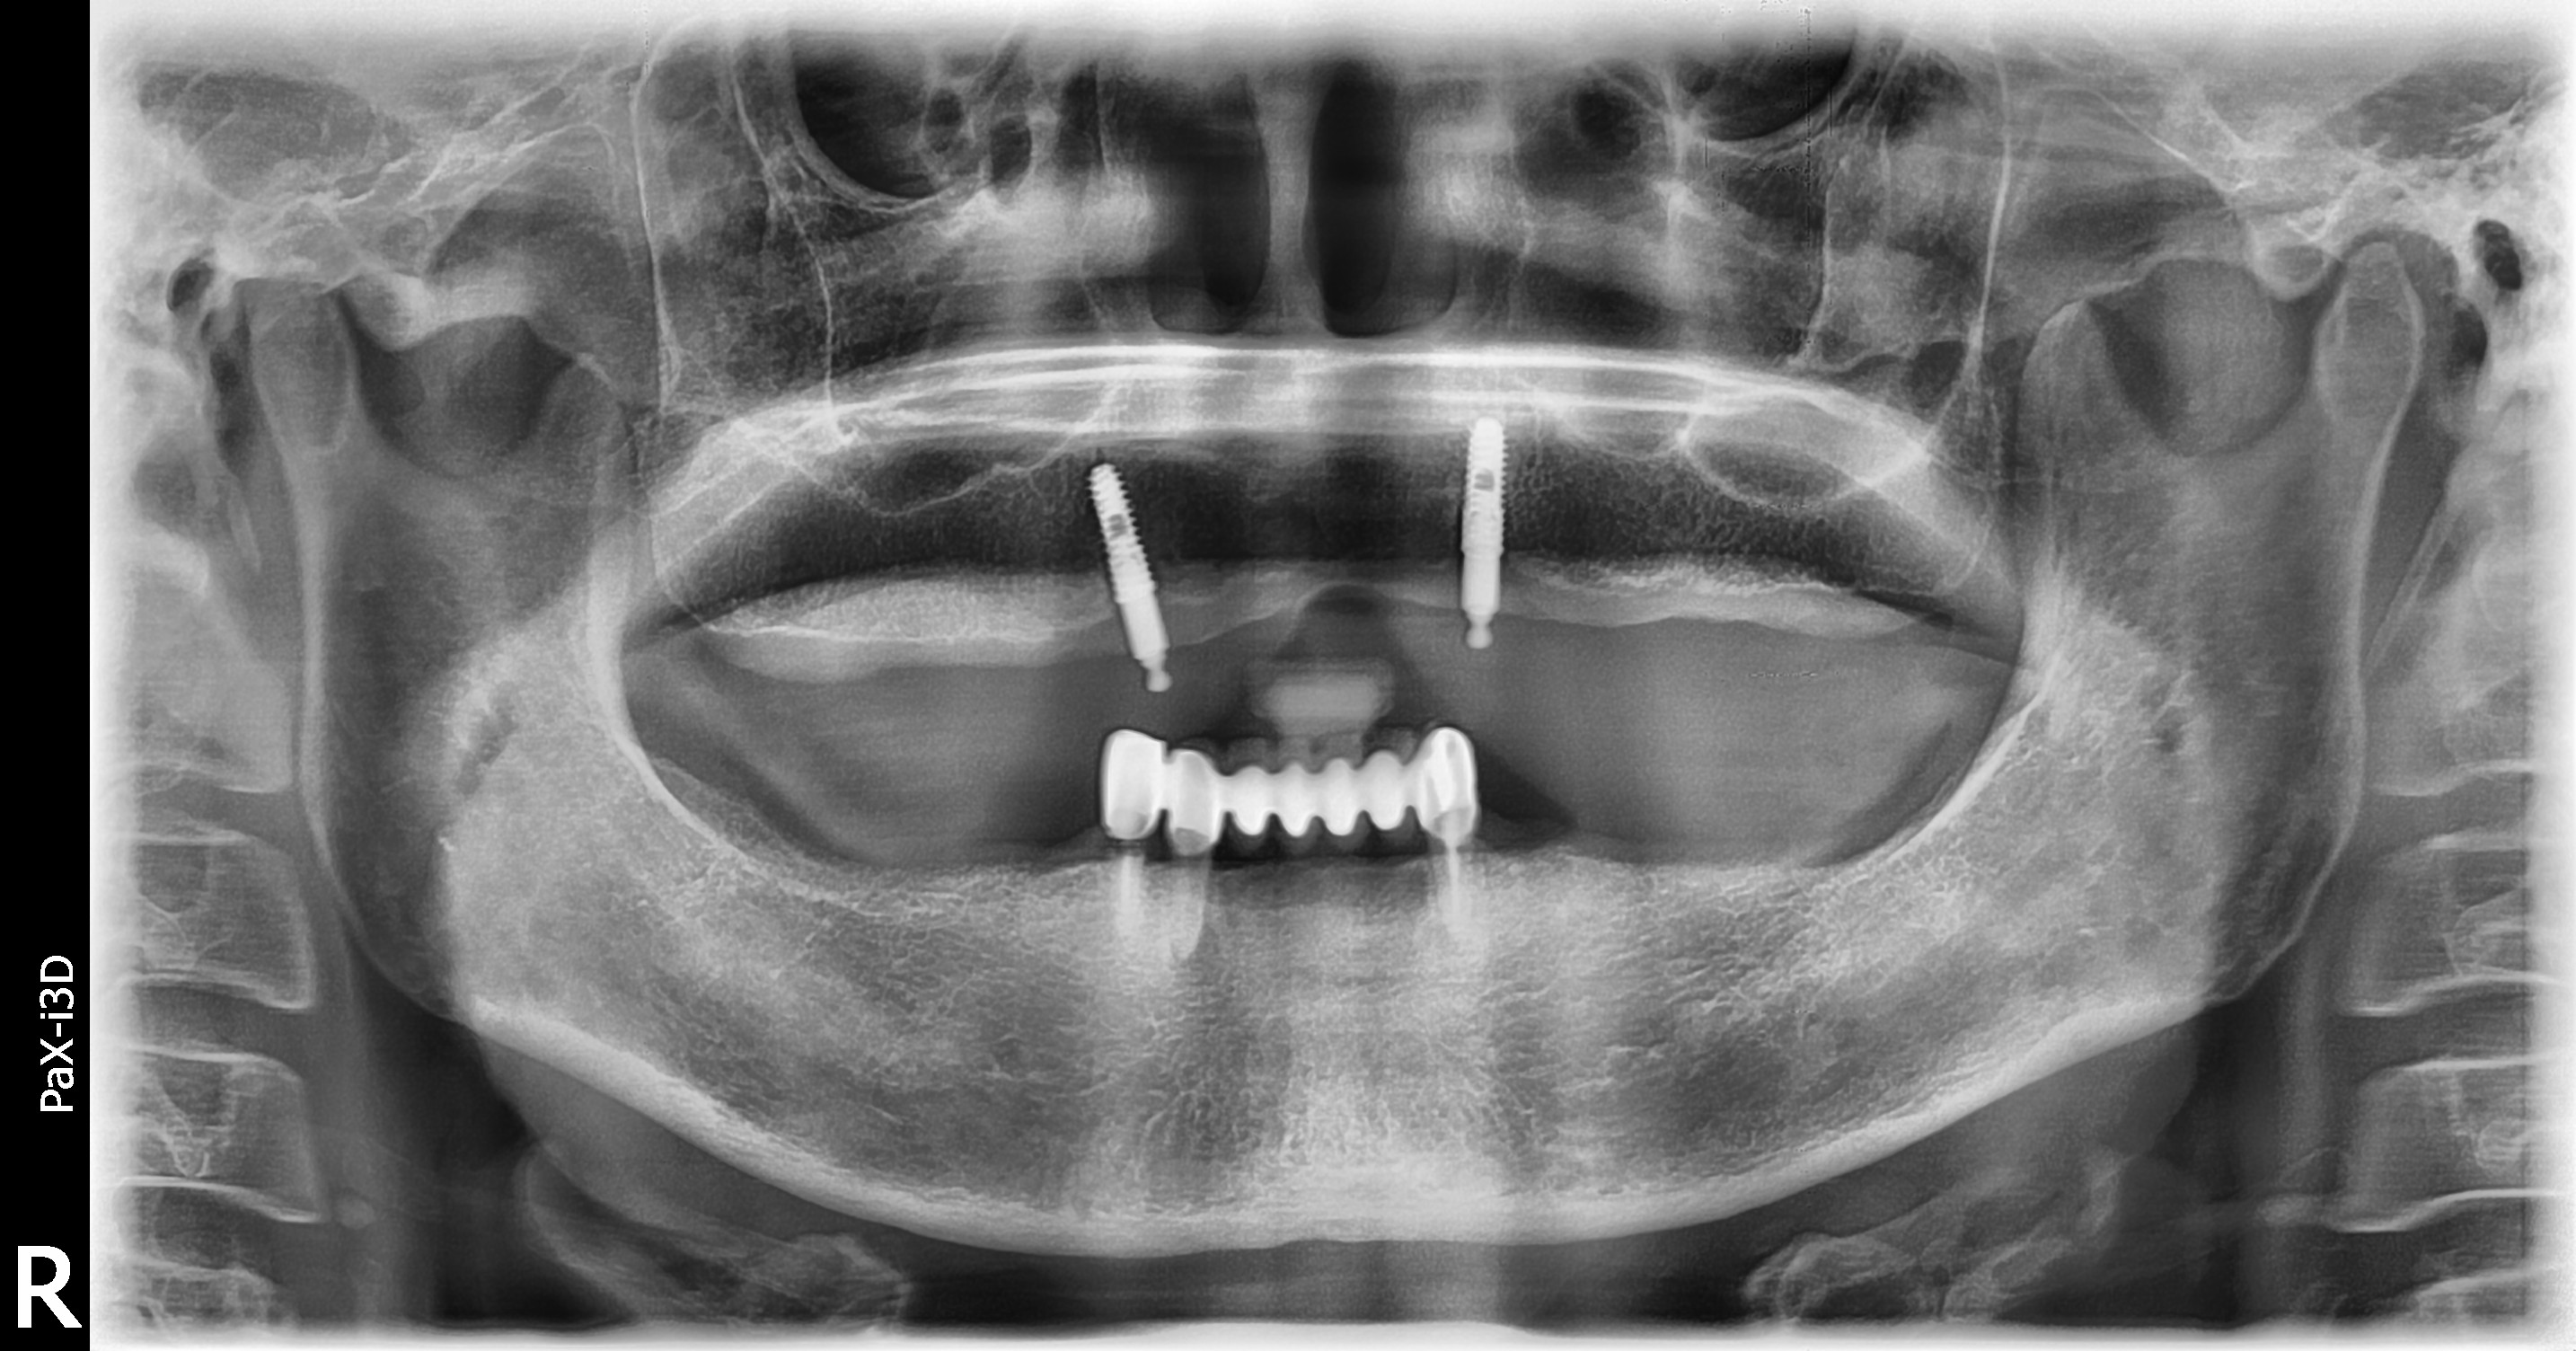

BEFOREAFTERAFTER(식립)AFTER(착용)

임플란트 틀니